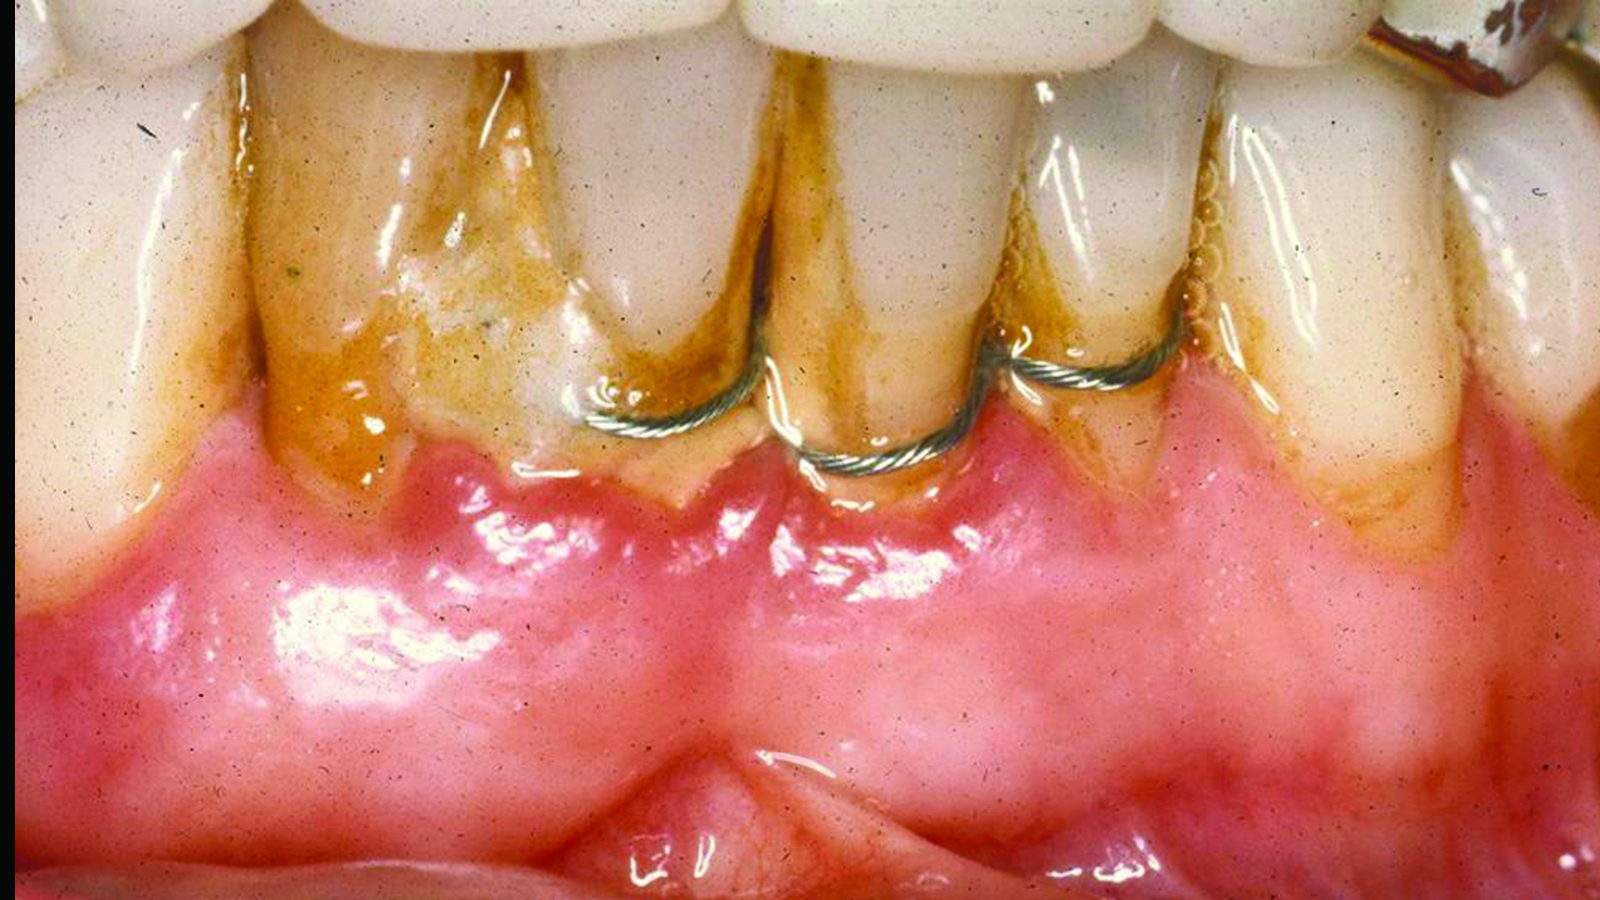

Fig 7. Case 2. Initial presentation of a patient with periodontitis (teeth Nos. 22 through 27). Generalized pocket depths of 6 mm to 7 mm were present, with wire splint on teeth Nos. 23 through 25.

Figure 7

Fig 8. Initial radiograph of the Case 2 patient, teeth Nos. 22 through 27. Fig 9. SRP resulted in the elimination of inflammation and remaining probing depths of 2 mm to 3 mm in Case 2 patient, 3 months post-therapy. (Fig 4 through Fig 9 are courtesy of Dennis Tarnow, DDS.)